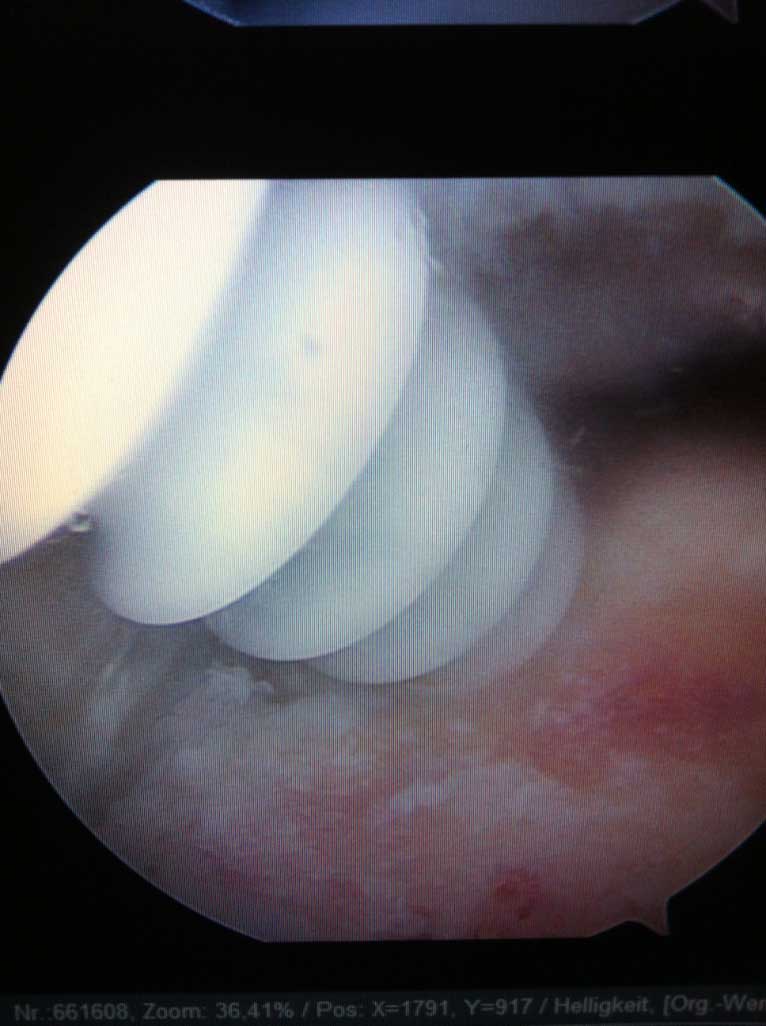

Das eigentliche Schultergelenk besteht aus 2 knöchernen Partnern, dem Oberarmkopf und der Gelenkpfanne, welche ein Teil des Schulterblattes ist. Dank der sehr flachen und eher kleinen Pfanne und wesentlich grösserem Kopf ermöglich die knöcherne Zusammensetzung des Gelenkes ein sehr grosses Bewegungsausmaß desselben.

Sowohl der Oberarmkopf als auch die Gelenkpfanne sind im Bereich der Gelenkfläche mit einem hyalinen Gelenkknorpel überzogen.

Wie auf der Bilddokumentation ersichtlich, wird die Kontaktfläche zwischen der kleinen knöchernen Pfanne und dem Kopf durch einen knorpeligen Ring, s.g. Labrum, der sich am Pfannenrand befindet, vergrössert.